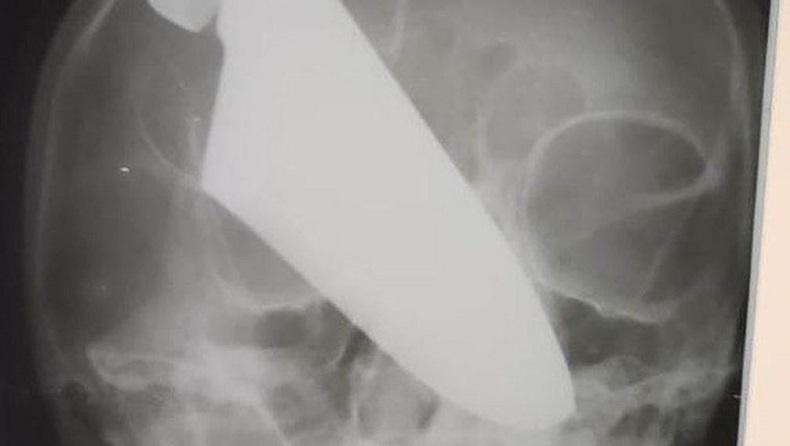

Wanita paruh baya berteriak minta tolong dengan pisau masih menancap di kepala. (Foto: Ministry of Health of Krasnodar Krai / East2west News)

MOSKOW, iNews.id - Seorang wanita paruh baya berteriak minta tolong dengan pisau masih menancap di kepala. Seorang laki-laki ditangkap atas insiden mengerikan tersebut.

Peristiwa ini terjadi di wilayah Krasnodar, Rusia. Diduga, korban yang berusia 60 tahun tersebut terlibat perselisihan rumah tangga dengan pelaku yang berusia 64 tahun.

Komite Investigasi Rusia (RIC) mengatakan telah terjadi pertengkaran antara pasangan itu. Beruntung korban bisa lari ke jalan dan meminta bantuan kepada warga.

“Warga setempat memanggil ambulans dan petugas penegak hukum ke tempat kejadian. Korban dibawa ke rumah sakit, di mana dia menerima perawatan medis,” kata seornang juru bicara RIC.